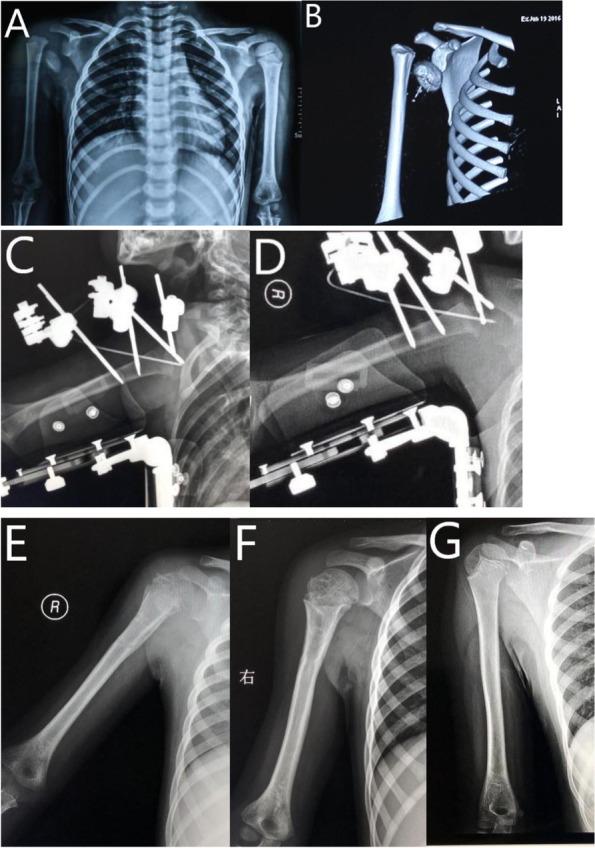

Between Jan 2014 and Jan 2019, 280 patients with unilateral proximal humeral fractures were retrospectively reviewed. Imaging and follow-up notes were reviewed for patients with a predilection for glenohumeral joint dislocation. Six (2.14%) patients between the ages of 5 and 10 years were confirmed as glenohumeral joint dislocation and included in the study. All these patients underwent closed reduction and external fixation under general anesthesia.

Out of 280 patients with proximal humeral fractures, only 6 patients, including 4 males and 2 females, were confirmed as glenohumeral joint dislocation. ROM was normal compared with the contralateral shoulder in every patient at the last follow-up. There was no case of radiological abnormality, including avascular necrosis or devascularization of the humeral head.

Glenohumeral dislocation is a rare entity associated with the proximal humerus fracture in children, with an overall incidence in our case series was 2.14%. Reduction and stabilization of such injury using an external fixator is a suitable choice for pediatric patients that failed closed reduction.